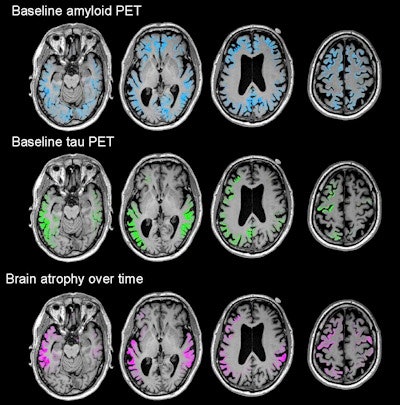

PiB-PET images revealed amyloid deposition in the prefrontal, posterior cingulate, and precuneus regions, as well as the lateral frontal and temporoparietal cortices. Flortaucipir-PET discovered maximum tau accumulation in the temporoparietal junction, the posterior cingulate, and the precuneus and moderate amounts in the dorsal frontal, occipital, and inferomedial temporal cortices.

The researchers longitudinally charted a pattern of atrophy that was greatest in the temporoparietal, posterior cingulate, precuneus, and dorsal frontal areas. All of those areas of atrophy coincidentally matched significantly elevated levels of flortaucipir.

Most importantly, those areas of tau buildup predicted subsequent atrophy in the same locations with more than 40% accuracy. Baseline PiB-PET scans, which detected amyloid, correctly predicted only 3% of future brain degeneration.